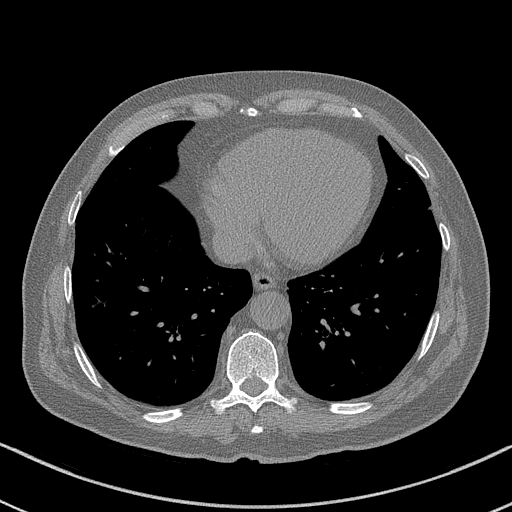

GT

FBP

HQS-CG

DuDoNet

Meta

Meta_re

EPNet

Qualitative Results Comparison. We also visualize the reconstruction results of these methods on AAPM-test and COVID-test datasets. As in the first three rows of Fig. 4, the reconstructed images from ours and retrained MetaInvNet show the best visualization quality on AAPM-test set across different angle numbers. Besides, our results show sharper details with the additional utilization of in the projection domain. When testing the reconstructed image on the COVID-test set, our result also gives sharper details but with more artifacts since the data distribution is very different. Although HQS-CG has achieved better quantitative results on the COVID-test dataset, the reconstructed image of their model in the fourth row is even smoother than FBP.